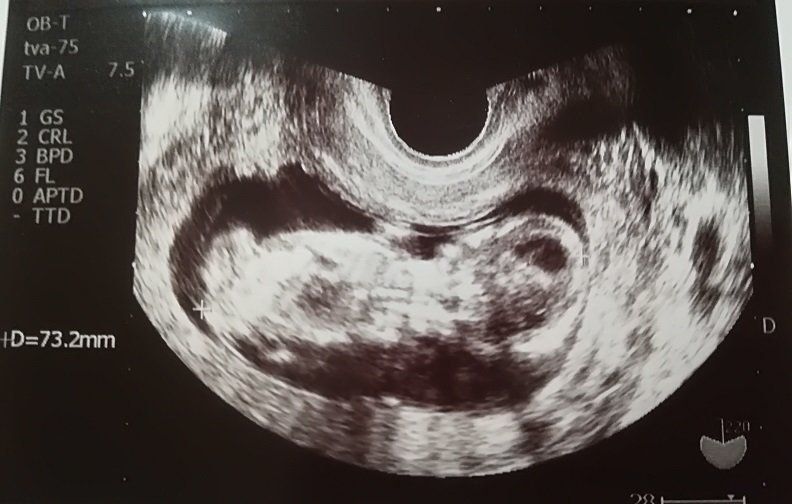

妊娠9週目のエコー写真

「もう、人の形をしている!」と驚きました。妊娠と同時に、里帰り先の産院を予約しました。その喜びをすべて吹っ飛ばしたのが、“つわり”。程度は違うものの皆さん経験するようですが、私は、家のビニール袋がすべてなくなるまで吐いてしまうという重症でした。内科で毎日点滴を受けながら乗り切り「母が食べられなくても、赤ちゃんて育つものだなぁ」と、感心しながら健診を受けていました。